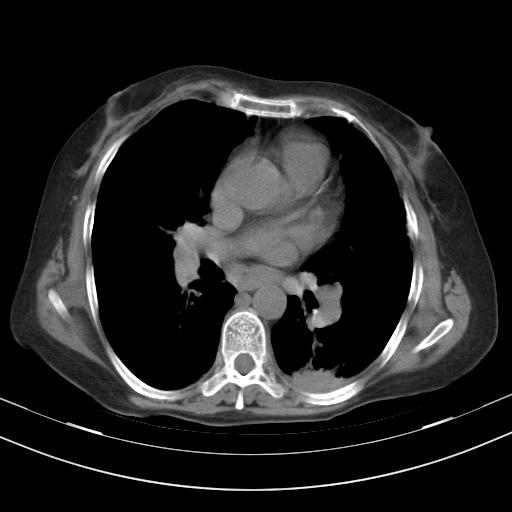

老年女性,嗜睡3天,意识模糊。轻咳,无发热。

两肺慢支炎伴感染,左侧胸腔积液。纵膈及双侧肺门淋巴结肿大建议复查。

1)两肺感染性病变;建议抗炎治疗后复查。2)纵隔淋巴结肿大。3)左侧胸腔积液。